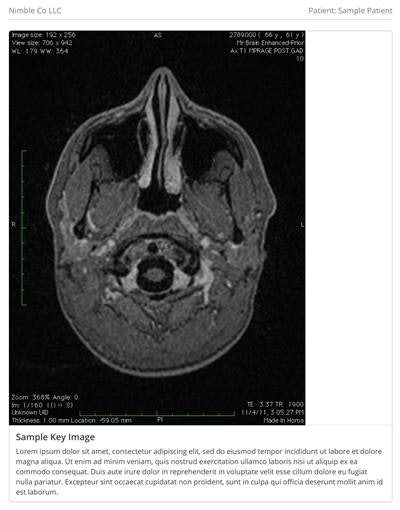

Accumulation of gadolinium in human cerebrospinal fluid after gadobutrol-enhanced MR imaging: A prospective observational cohort study. Nehra AK et al, Radiology, August 2018. To learn more about this paper, click here.

In the current study, Dr. Avinash Nehra and colleagues from the Mayo Clinic in Rochester, MN, used samples drawn from lumbar punctures to detect gadolinium in the cerebrospinal fluid of adult and pediatric patients after they received a macrocyclic GBCA. The trace elements were found even in patients who had normal renal function and an undamaged blood-brain barrier.

That's important, because previous speculation had theorized that gadolinium made its way into brain tissue only if the blood-brain barrier had been compromised. The findings by Nehra et al indicate that cerebrospinal fluid may be the route gadolinium follows to enter brain tissue -- even in healthy patients.